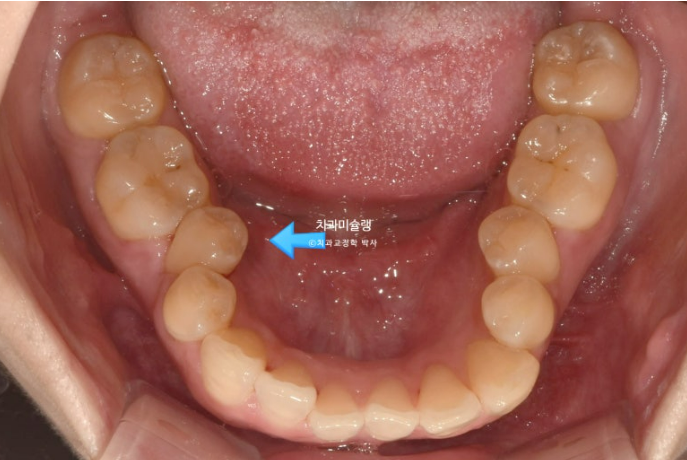

파란화살표는 가위교합 원인 치아입니다.

24.06